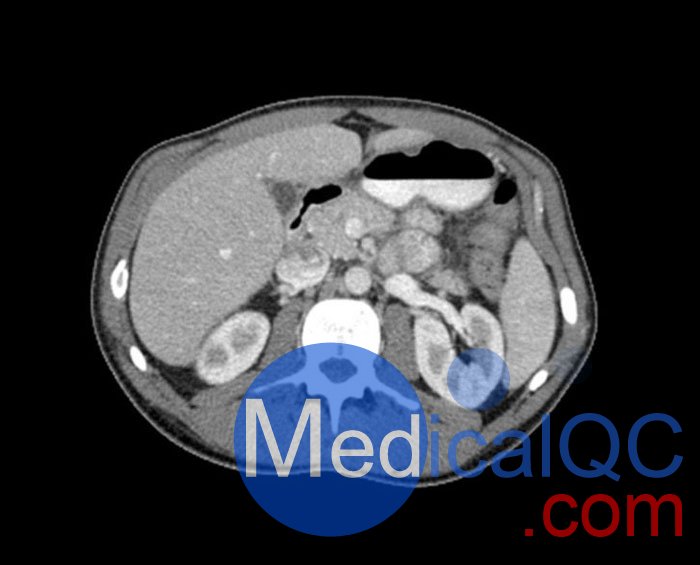

WEK57-01門靜脈期軀干模體,WEK57-01軀干模型模擬了門靜脈期的造影劑增強(qiáng)胸部、腹部和骨盆。它覆蓋了會陰的第二胸椎。

右側(cè)有髂淋巴結(jié)腫塊。

真實模擬脈管系統(tǒng)、骨骼和軟組織,包括肺、心臟、肝臟、膽囊、胰腺、脾臟、腎上腺、腎臟、胃、小腸、結(jié)腸、膀胱和前列腺。

右側(cè)髂外淋巴結(jié)腫塊。

WEK57-01門靜脈期軀干模體,WEK57-01軀干模型成像效果圖: